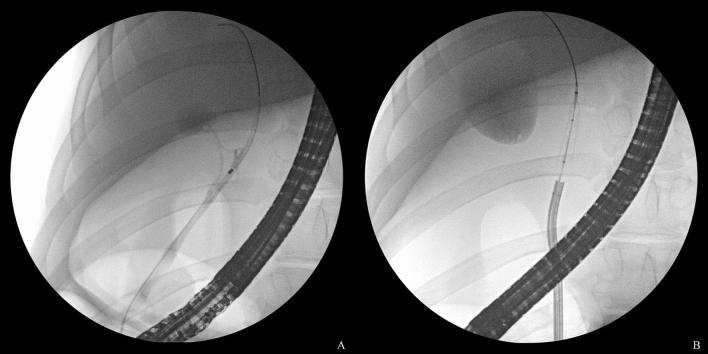

Figure 2.

After obtaining the cholangiogram and achieving guidewire placement in the bile duct (A), a cholangioscope is inserted, and radiofrequency ablation with a balloon-based catheter is subsequently performed under cholangioscopic and fluoroscopic guidance (B).